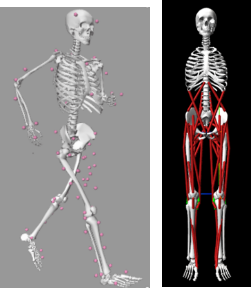

图注:FEM 有限元分析、力动学分析、骨与关节数字建模

图注:逆动力学分析